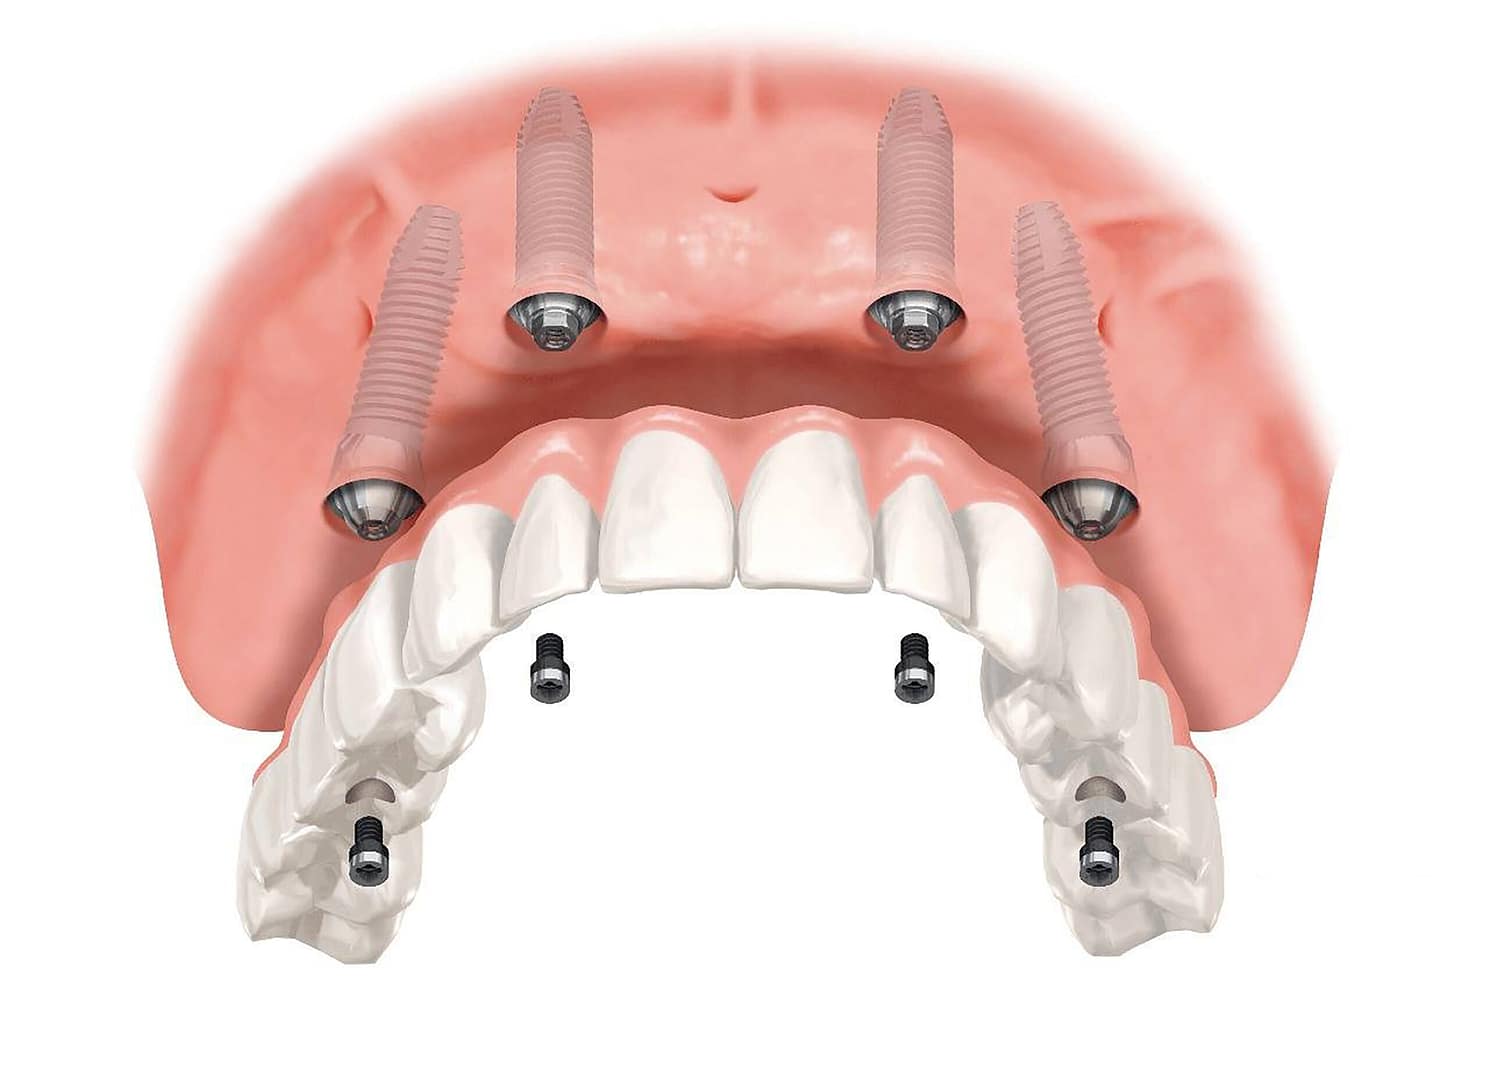

Un implante dental es una pequeña pieza de titanio que se coloca en el hueso maxilar para reemplazar la raíz de un diente perdido. Encima se coloca una corona que imita al diente natural en forma y función.